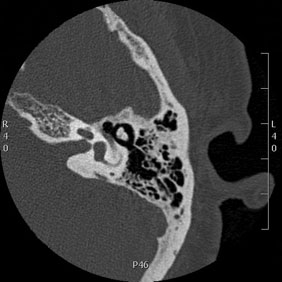

Tomografía computarizada Oídos

< Volver a "Tomografía Computarizada (TC) con Inteligencia artificial"Se utiliza para el estudio de las estructuras del oído interno, los peñascos o las celdas mastoideas.